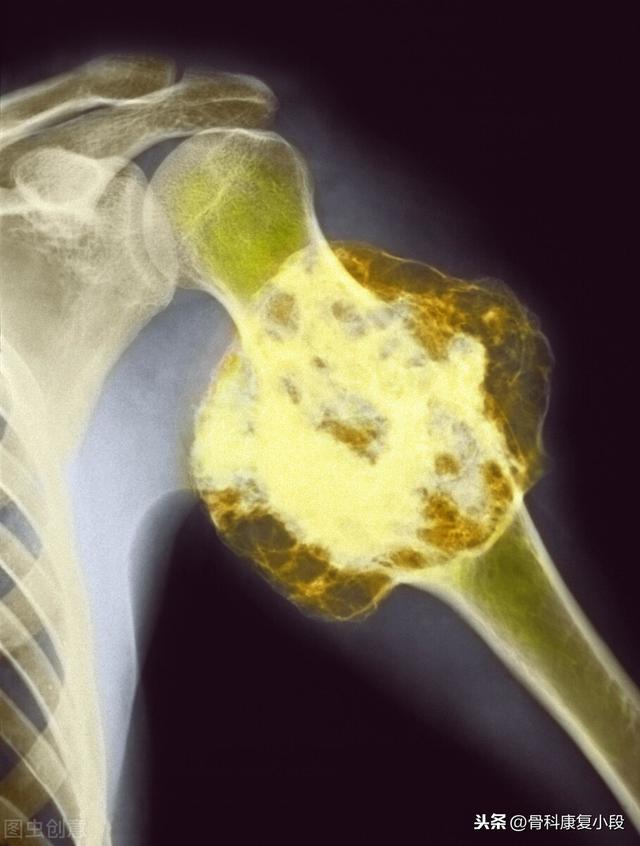

Quels sont les symptômes des métastases osseuses ? Le premier symptôme est la douleur. Le site de la métastase osseuse ressentira une douleur due à la destruction de l'os, qui peut ne pas présenter de symptômes évidents ou une douleur intermittente au début, mais comme la tumeur détruit l'os normal de manière progressive et s'aggrave peu à peu, la douleur dans le site métastatique s'aggravera également progressivement. Sur le plan clinique, il arrive que nous rencontrions un cas de douleur osseuse dans une certaine partie du corps, qui résulte d'une métastase osseuse d'une tumeur maligne. Il y a quelque temps, j'ai rencontré un cas, 40 ans, douleur à l'épaule, j'ai pensé à une épaule gelée, j'ai frotté quelques jours d'huile médicinale sans voir d'amélioration, mais de plus en plus de douleur, alors je suis allé à l'hôpital pour un examen, j'ai fait une imagerie par résonance magnétique, l'omoplate a été mangée par un morceau de (tumeur), considérant qu'il s'agissait d'une métastase osseuse, puis j'ai fait un scanner thoracique, un nodule dans le poumon droit, puis j'ai fait une biopsie pour faire la pathologie, qui était une métastase osseuse d'un cancer du poumon. Les informations sont les suivantes.

Sur le site des métastases osseuses, étant donné que le tissu osseux normal est détruit et remplacé par du tissu tumoral et que les cellules tumorales prolifèrent constamment, des ombres de masses de tissus mous peuvent être observées sur de nombreux sites de métastases osseuses, et peuvent être palpées si la masse se trouve dans une zone superficielle. En outre, l'érosion du tissu osseux normal par le tissu tumoral entraîne également la destruction et l'affaiblissement de la structure osseuse normale, de sorte que des fractures peuvent se produire sous l'effet de forces externes normales, appelées fractures pathologiques (figure ci-dessous). Outre la douleur et la fracture pathologique, les métastases au niveau de la colonne vertébrale peuvent également se manifester par une compression des racines nerveuses de la colonne vertébrale avec des symptômes tels qu'une déficience sensorielle, une faiblesse musculaire et, dans certains cas, une hypercalcémie.

La tumeur à cellules géantes de l'os est une tumeur soluble provenant de la matrice spongieuse de l'os, survenant entre 20 et 40 ans, plus souvent chez les femmes que chez les hommes, et prédominant dans les épiphyses des os tubulaires longs. Le principal symptôme est la douleur, qui augmente avec la croissance de la tumeur. Elle est plus fréquente à l'extrémité inférieure du fémur ou à l'extrémité supérieure du tibia. Si le cartilage articulaire est touché, cela aura un impact sur la fonction de l'articulation.